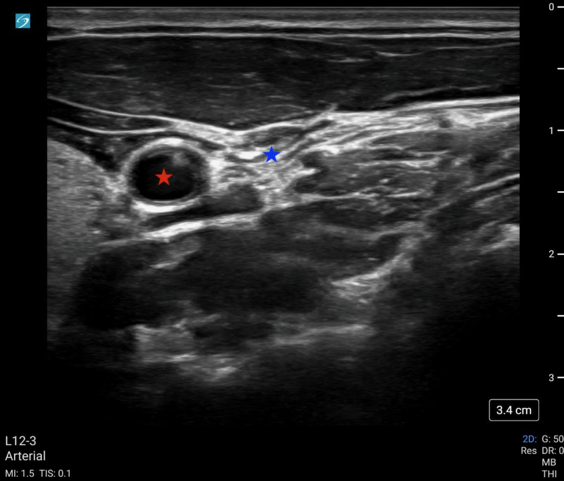

Compression

Perhaps the most accessible version of sonographic pulse check is the compression method. Using standard grey scale (B-mode) imaging, the operator uses the ultrasound probe to compress either the carotid artery or femoral artery until the accompanying major vein is completely collapsed, termed POCUS femoral artery compression (POCUS-FAC) or carotid artery compression (POCUS-CAC). In cases where ROSC has been achieved, the artery will not completely collapse and should display pulsatility.

May2025Sonographic Fig 1 pocus cac.pngImage 1: POCUS-CAC with a fully compressed IJ (blue star) without compression of the common carotid artery (red star).

Video 1: POCUS-CAC showing complete collapse of the IJ with pulsatility of the adjacent carotid artery.